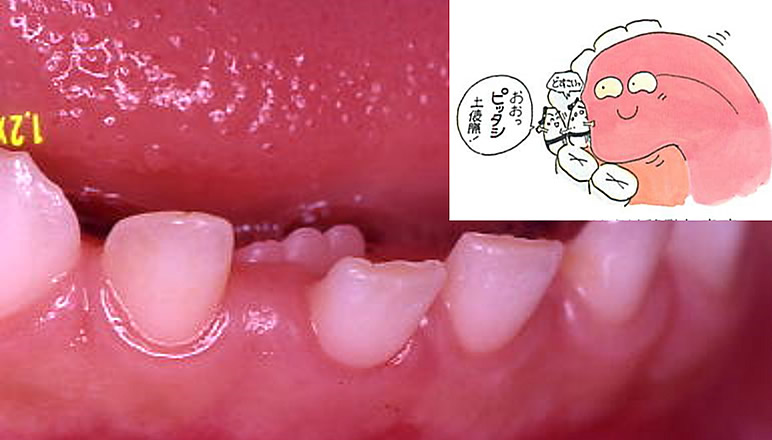

第39回 床矯正フォローアップセミナー】DVD☆症例検討 側方拡大。9月8日(日)・9日(月)の報告〈その3〉|矯正歯科医・小児歯科医。非抜歯症例(左上犬歯牽引) | ひらぎし通り矯正歯科。最新入荷分★ロウカット玄米 東洋ライス 金芽米 ローカット玄米 無洗米水洗い不要。。上顎左側犬歯の埋伏に対して残存する上顎左側乳犬歯を抜歯して。セミナー実施報告|矯正歯科医・小児歯科医のためのセミナー。Amazon.co.jp: 臨床家のための床矯正治療: バイオファンク。埋伏歯・受け口・がたがた・9歳女子【K.T様】 京都さわだ矯正歯科。

※収録内容につきましてはDVD画像にてご確認ください。埋伏歯・受け口・がたがた・9歳女子【K.T様】 京都さわだ矯正歯科。

この機会に、ぜひご入札下さい。小児矯正で拡大床とリンガルアーチを使用し軽度の反対咬合を改善。